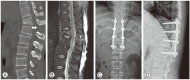

Treatment of thoracolumbar fracture

The most common fractures of the spine are associated with the thoracolumbar junction. The goals of treatment of thoracolumbar fracture are leading to early mobilization and rehabilitation by restoring mechanical stability of fracture and inducing neurologic recovery, thereby enabling patients to return to the workplace. However, it is still debatable about the treatment methods. Neurologic injury should be identified by thorough physical examination for motor and sensory nerve system in order to determine the appropriate treatment. The mechanical stability of fracture also should be evaluated by plain radiographs and computed tomography. In some cases, magnetic resonance imaging is required to evaluate soft tissue injury involving neurologic structure or posterior ligament complex. Based on these physical examinations and imaging studies, fracture stability is evaluated and it is determined whether to use the conservative or operative treatment. The development of instruments have led to more interests on the operative treatment which saves mobile segments without fusion and on instrumentation through minimal invasive approach in recent years. It is still controversial for the use of these treatments because there have not been verified evidences yet. However, the morbidity of patients can be decreased and good clinical and radiologic outcomes can be achieved if the recent operative treatments are used carefully considering the fracture pattern and the injury severity.